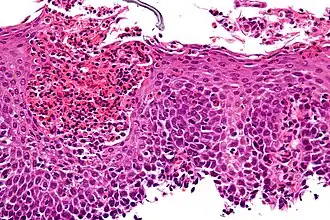

| Esofagite eosinofílica vista sob microscópio. | |

O diagnóstico se baseia nos sintomas e nas biópsias do esôfago, que são obtidas através de endoscopia digestiva alta. As amostras obtidas pelas biópsias devem ser examinadas por um patologista, que faz o diagnóstico de esofagite eosinofílica quando encontra mais de 15 eosinófilos em campo de grande aumento.